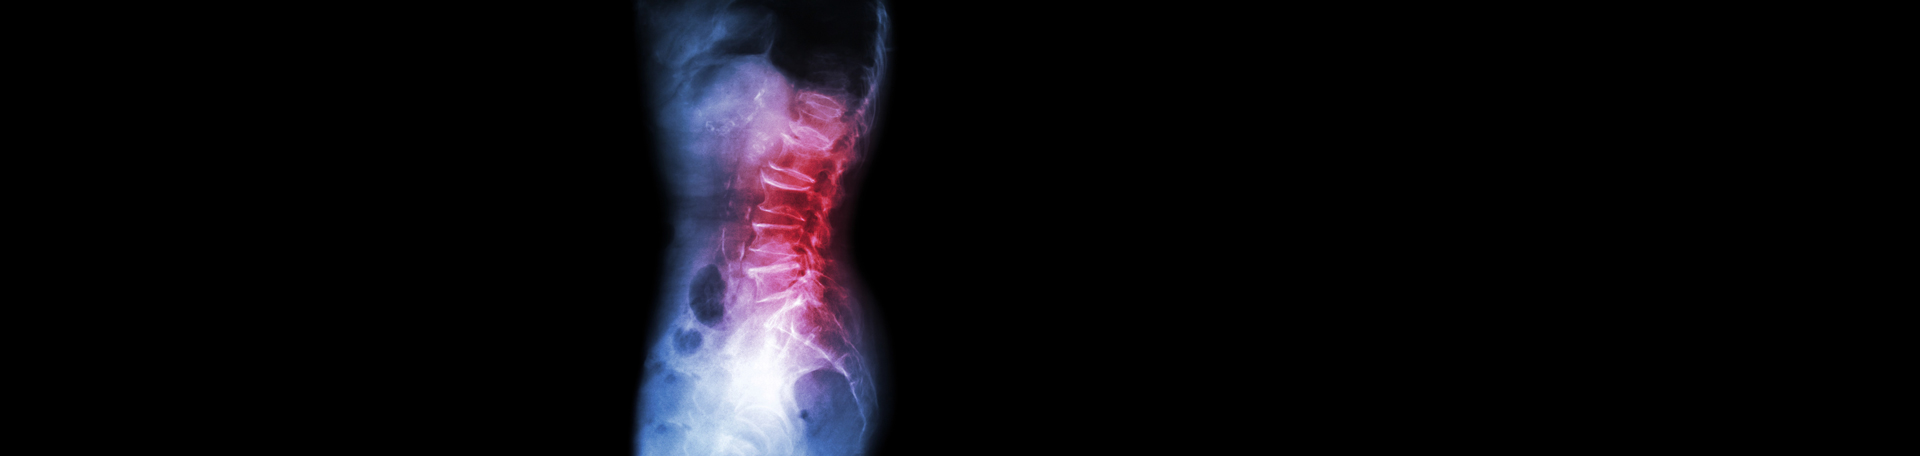

Suffering from persistent back pain? You may be dealing with spondylolisthesis, a condition where one vertebra – spinal bone – slips out of place over the one beneath it. This spinal misalignment often ends with nerve compression, causing pain, stiffness, and sometimes debilitating symptoms in the back and legs. Spondylolisthesis can develop due to various factors, including genetics, injury, or degenerative changes. Accurate diagnosis is critical for containing this condition, and advanced imaging methods are vital. Chiropractic care is successful at managing spondylolisthesis.

Imaging tools such as X-rays and MRI play a critical role in detecting spondylolisthesis and its impact on the spine. According to McCormick and Perloff, the American Journal of Physical Medicine & Rehabilitation emphasizes that X-rays are good in ascertaining structural issues like spondylolisthesis, while MRI offers more detailed information on nerve involvement and soft tissue damage. (1) Together, these imaging modalities present a comprehensive understanding of the condition, assisting healthcare providers plan more targeted treatment strategies. The more information, the better!